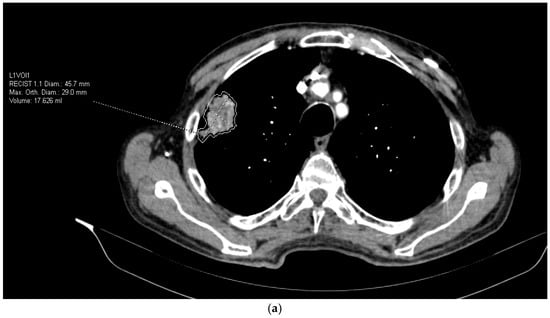

- Lesion morphology: maximum diameter (mm), volume (mm3), shape irregularity;

- Texture features: mean attenuation, entropy, skewness, kurtosis, gray-level co-occurrence metrics;